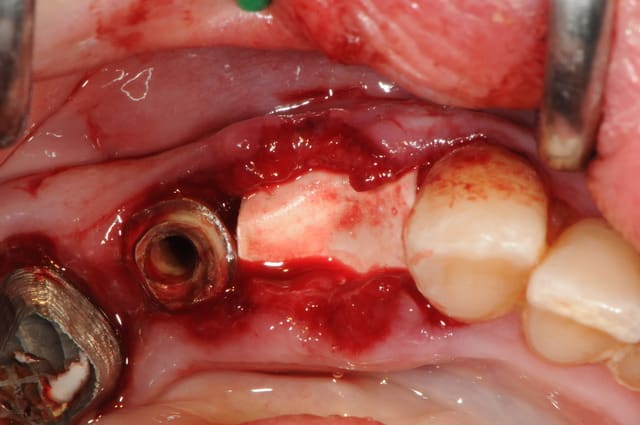

la preuve par 9...

3ième photo , c'est j+3 mois.